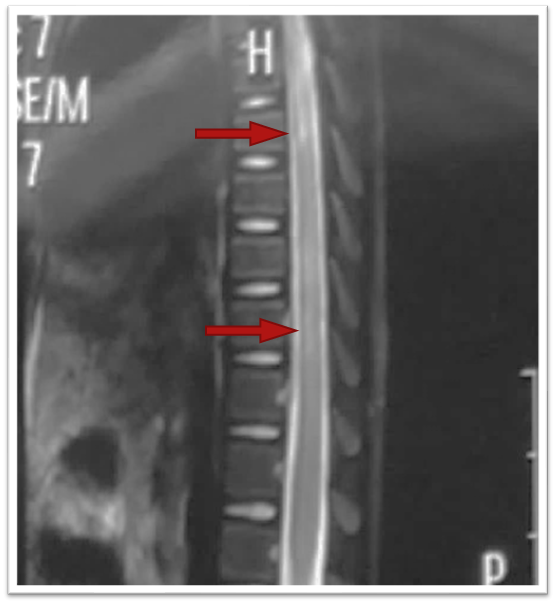

图片

正中间灰色的竖条就是脊髓,箭头指的,灰色中的白色条纹,就是脊髓损伤的表现。

再比如,脊柱被拉长,因为弹性好又回去了,但脊髓已经被“拉伤”了。